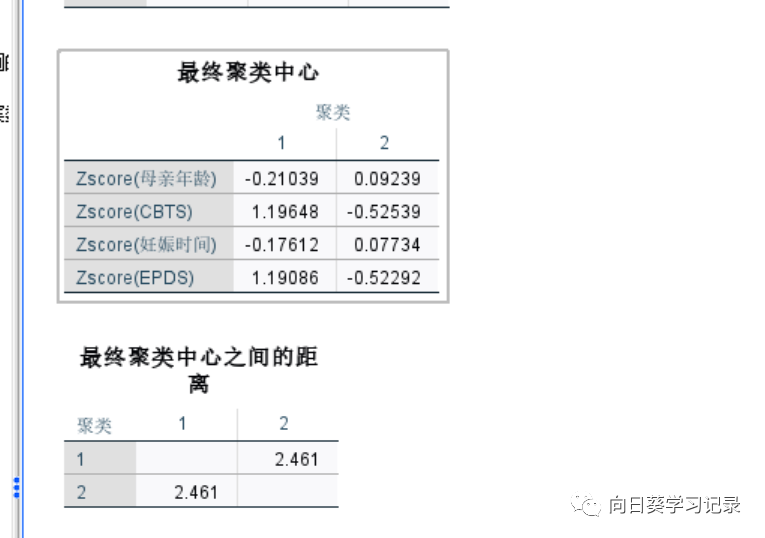

第一个 为初始聚类中心,初始聚类中心是SPSS自动选择的一个实际样本,选择原则是所有变量构成的空间中的距离尽可能远,而且尽可能地分布在空间中,需要注意的是选择会和个案排列的顺序有关,可以在计算之前打乱排列顺序

下一幅图是迭代记录,可以开出聚类中心变化越来越小,直至趋近于0,在第11次迭代的时候终止,聚类中心收敛

下一幅图是最终聚类中心以及他们之间的距离.最终聚类中心也说明了他们的特征,比如1类的CBTS和EPDS就比较高,而2就低,说明1组的焦虑程度比2组要高

最后是给出了每个聚类的个案数和ANOVA检验,ANOVA表示每个变量在不同类别之间是否存在显著差异,若存在的越多则表明聚类效果越好,根据图中可知,CBTS和EPDS对聚类有贡献,且EPDS的F值最大,说明EPDS对聚类的影响最大,CBTS次之,妊娠时间最小。1类为119 2类为271